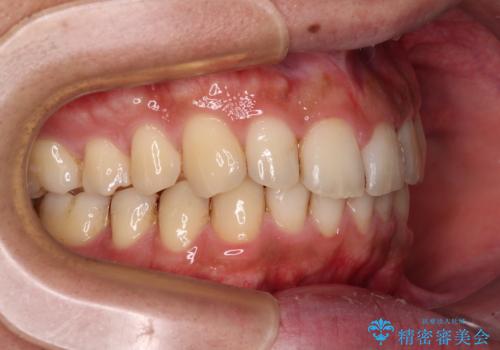

前歯のデコボコをスッキリ改善 インビザライン矯正

- 上下前歯のデコボコを気にして来院された患者様です。

全体的に叢生は軽度であったため、インビザラインにて矯正治療を行うこととしました。

デコボコの改善はもちろん、下顎前歯が隠れてしまうディープバイトも一緒に改善することができ、奥歯への負担を軽減することができました。